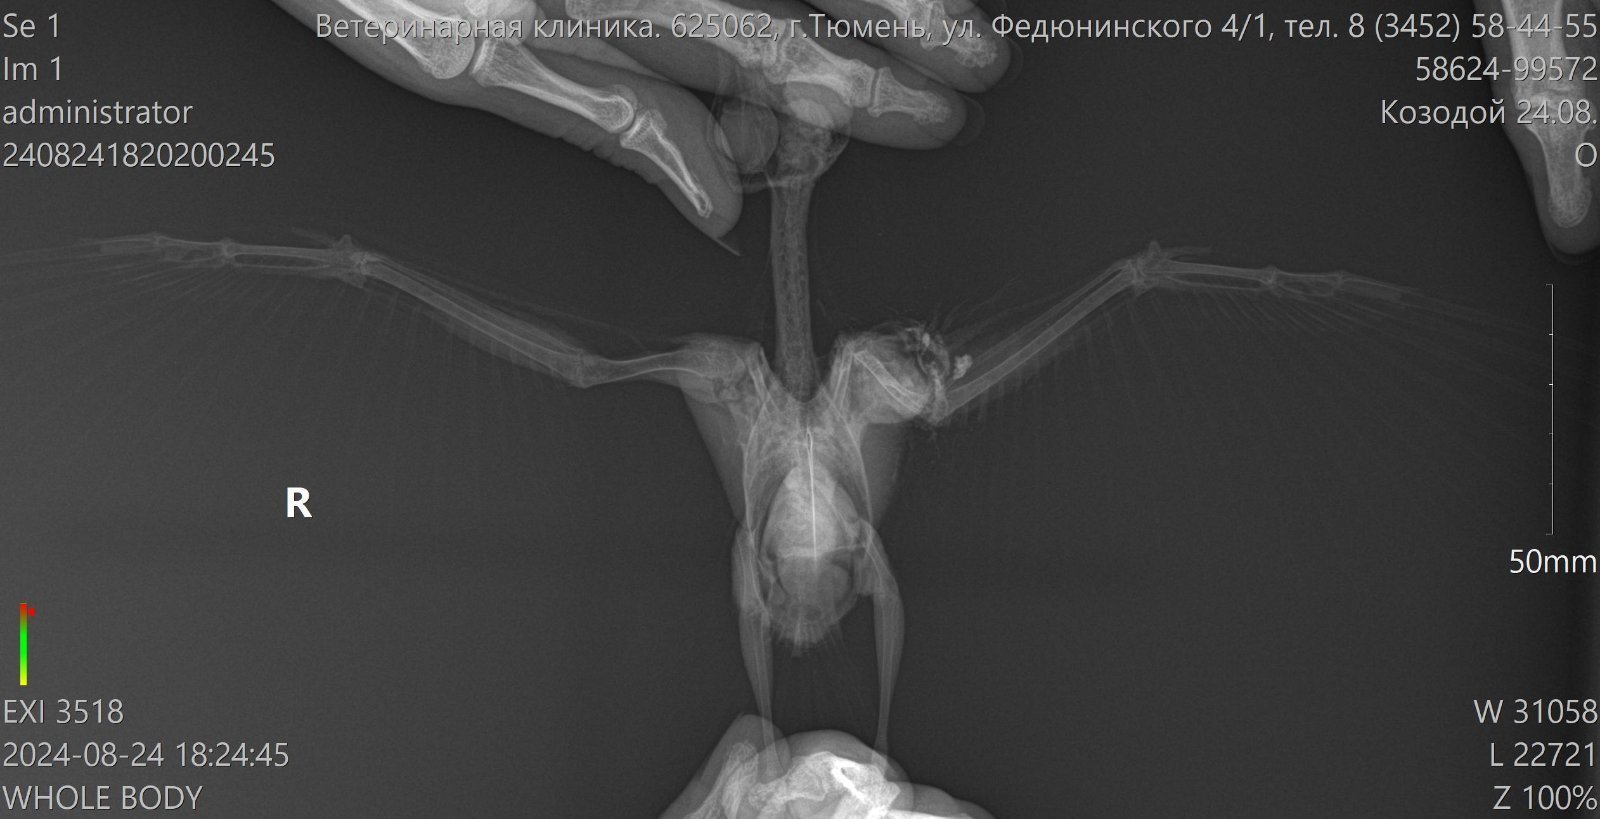

Голубенок, подобран 23.08.24, перелом крыла, сделан рентген, кисти со смещением. Рекомендовали усыпить, тк на улицу нельзя его уже, ну или фиксировать крыло и искать ПМЖ. Крыло зафиксировали.

перелом крыла, сделан рентген, кисти со смещением

покажите пожалуйста рентген

Рентген не тот отправила и удалить не знаю как, вот этот голубя моего

да уж, я как первый снимок увтдела- упала...

На "вашем" снимке- перелом токтевой кости,эпифизарный. Зарастет.

Надол остеогенон и артрогликан давать, 3-4 недели. Состричь длинные перья- чтобы не мешали укладыванию крыла анатомически правильно. Покой, никаких полетов как минимум 21 день (попыток полетов)